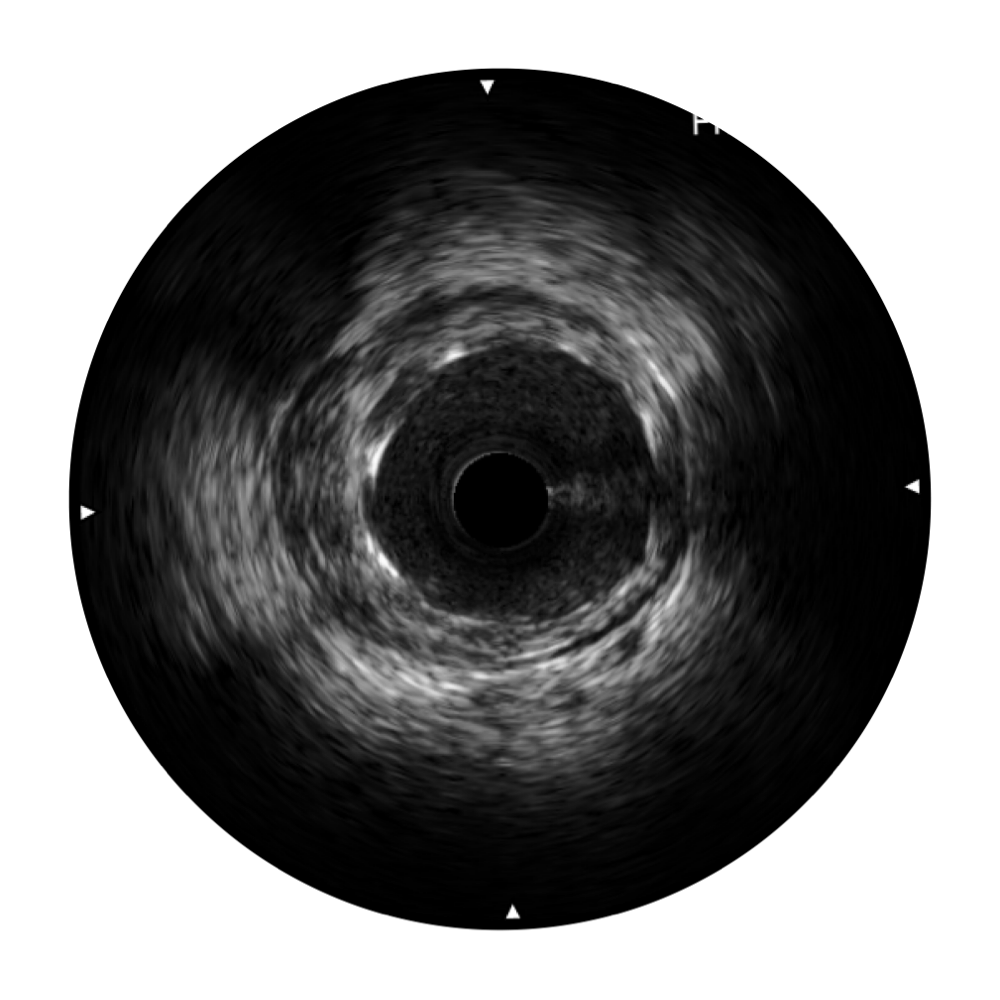

传统IVUS图像

对比传统IVUS导管成像,db真人体育官网宽频IVUS图像的近场支架梁显影更细腻,远场中膜外血管仍清晰可辨,兼顾远中近,兼顾分辨力与穿透深度